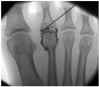

The terminology 'Morton's neuroma' may represent a simplification of the clinical condition as the problem may not be a benign tumour of the nerve, but neuropathic foot pain associated with the interdigital nerve.Foot and ankle pathomechanics leading to metatarsalgia, clinical examination and differential diagnosis of the condition and imaging of the condition, for differential diagnosis, are discussed.Nonoperative management is recommended initially. Physiotherapy, injections (local anaesthetic, steroid, alcohol), cryotherapy, radiofrequency ablation and shockwave therapy are discussed.Operative treatment is indicated after nonoperative management has failed. Neuroma excision has been reported to have good to excellent results in 80% of patients, but gastrocnemius release and osteotomies should be considered so as to address concomitant problems.Key factors in the success of surgery are correct diagnosis with recognition of all elements of the problem and optimal surgical technique. Cite this article: EFORT Open Rev 2019;4:14-24. DOI: 10.1302/2058-5241.4.180025.